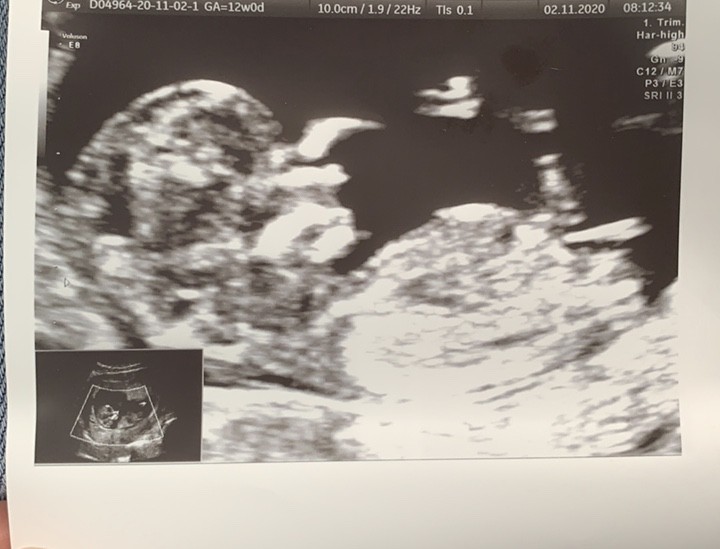

Witam w 19 tygodniu ciąży dowiedziałam się ze będę miała dziewczynkę w 20 tyg okazało się jednak , że to chłopak. Sama już nie wiem bo na jednym usg widać na pewno dziewuche a na drugim chłopca. Może to pempowina ?? Może ktoś mi pomoże rozwiązać ta zagadkę